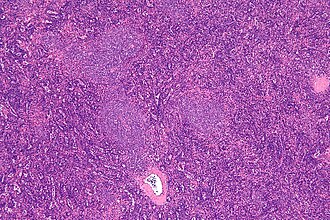

Template:Px Small lymphocytic lymphoma. H&E stain. | |

| LM | mixed population of lymphoid cells with "proliferation centers": (1) nodular collections of larger cells (~ 1.5x the size of resting lymphocyte ~ 12-15 micrometers) with nucleoli) - surrounded by (2) small dark cells (~ size of resting lymphocyte ~ 8-10 micrometers) - predominant population, lack nucleolus |

Features in a lymph node:[4]

- Mixed population of lymphoid cells with "proliferation centers" - key feature:

- Larger cells (~ 1.5x the size of resting lymphocyte ~ 12-15 micrometers):

- Nucleoli.

- Form (nodular) collections.

- Small dark cells (~ size of resting lymphocyte ~ 8-10 micrometers):

- Predominant population.

- Lack nucleolus.